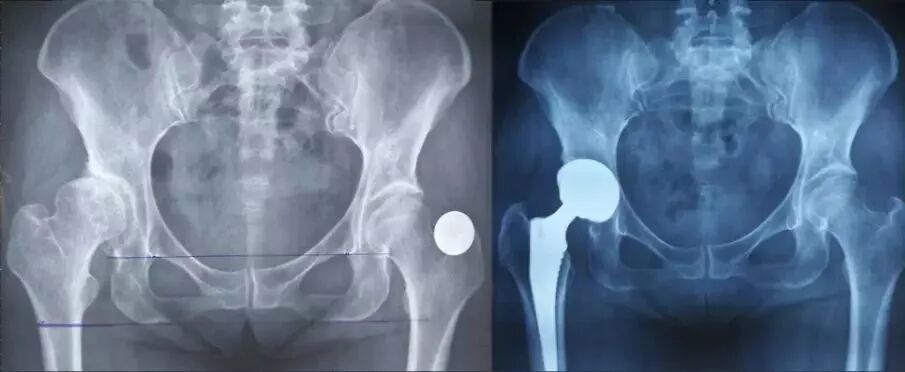

肢体长度:

真实长度(髂前上棘到内踝长度)测量即可;

影像学长度(耻骨下沿连线通过双侧股骨同一高度),有些患者可能影像学上看着不等长,这时候考虑是处于外旋位,摆到正常内旋位即可准确判断是否等长。

髋臼位置:恰好贴近泪滴外侧缘,臼杯缘应位于髋臼内外侧壁之间;